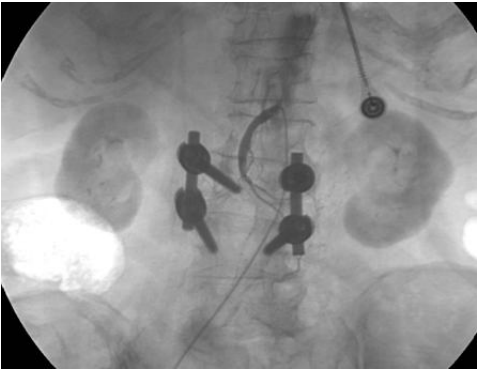

76.病人急性腹痛前來求診,理學與電腦斷層檢查懷疑腸道缺血(bowel ischemia),遂執行血管攝 影檢查,請依所附之下圖回答下列三題:1.圖中影像中央顯示為那一條血管?

(A)肝動脈 (B)脾動脈 (C)胃十二指腸動脈 (D)上腸系(繫)膜動脈

77.2.正常情況下該血管之血管攝影在靜脈相(venous phase)可呈現那條血管之顯影? (A)脾靜脈(splenic vein) (B)下腸繫膜動脈(inferior mesenteric vein) (C)門脈靜脈(portal vein) (D)下腔大靜脈(inferior vena cava)

78.3.該血管之末端沒有顯影,最可能原因為何? (A)正常變異 (B)急性血栓 (C)血管撕裂 (D)對比劑外漏